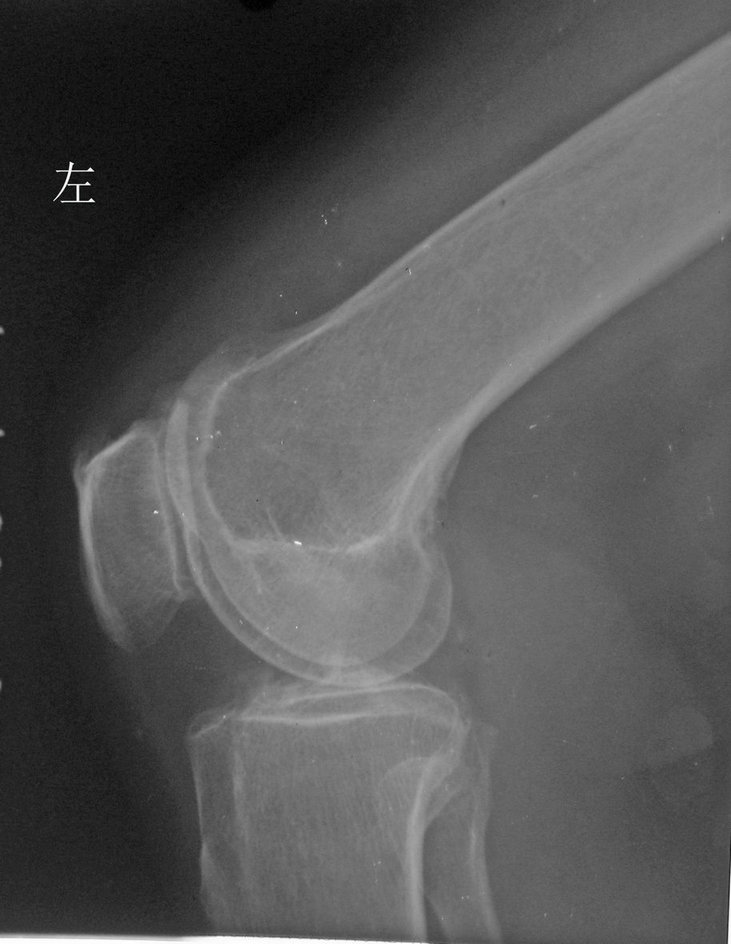

以下是引用拾荒者在2010-7-5 21:08:00的发言:[br]1.膝关节退行性变;2.颈椎未见明显异常。

以下是引用hexue在2010-7-5 22:47:00的发言:[br]1.膝关节退行性变;2.颈椎未见明显异常。 [br] [br]

以下是引用随光逐影在2010-7-6 7:11:00的发言:[br]病例1:双膝关节退行性骨关节病。[br]病例2:1)颈椎未见明确异常。2)一侧下颌智齿横位阻生。